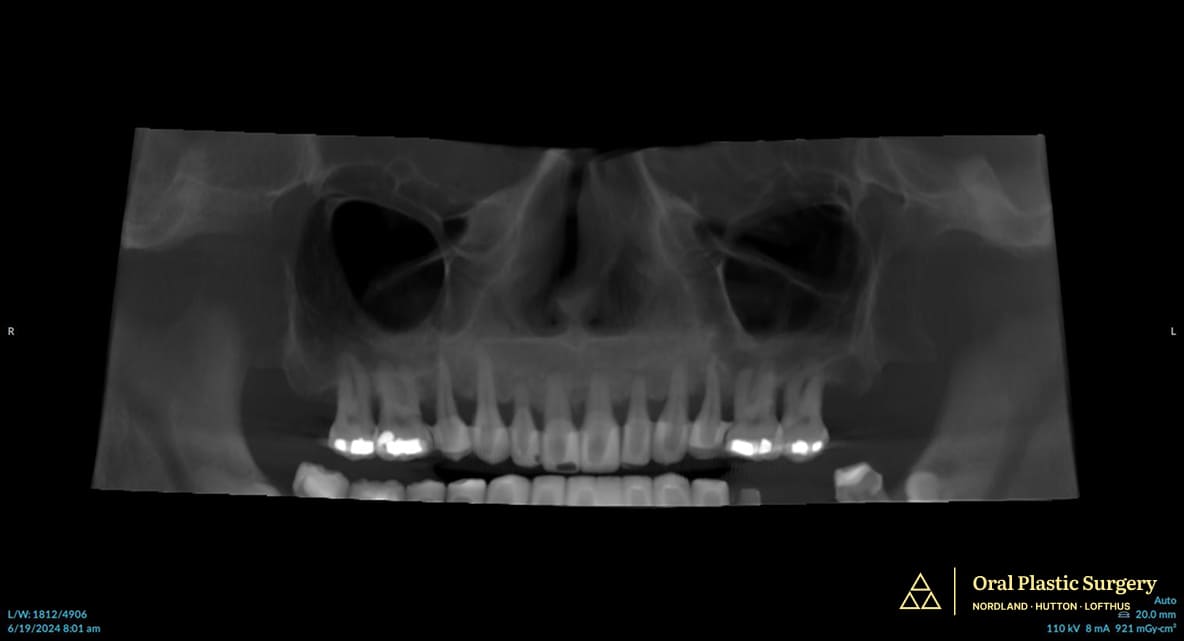

- Digital Planning: Intraoral scanning, CBCT imaging, and comprehensive digital workflow.

Digital planning technology mapped out the precise placement of Phil’s seven implants, including two pterygoid implants for added stability.

Before surgery: advanced periodontal disease and bone loss made saving the teeth impossible. Full-arch implant treatment was the best long-term solution.